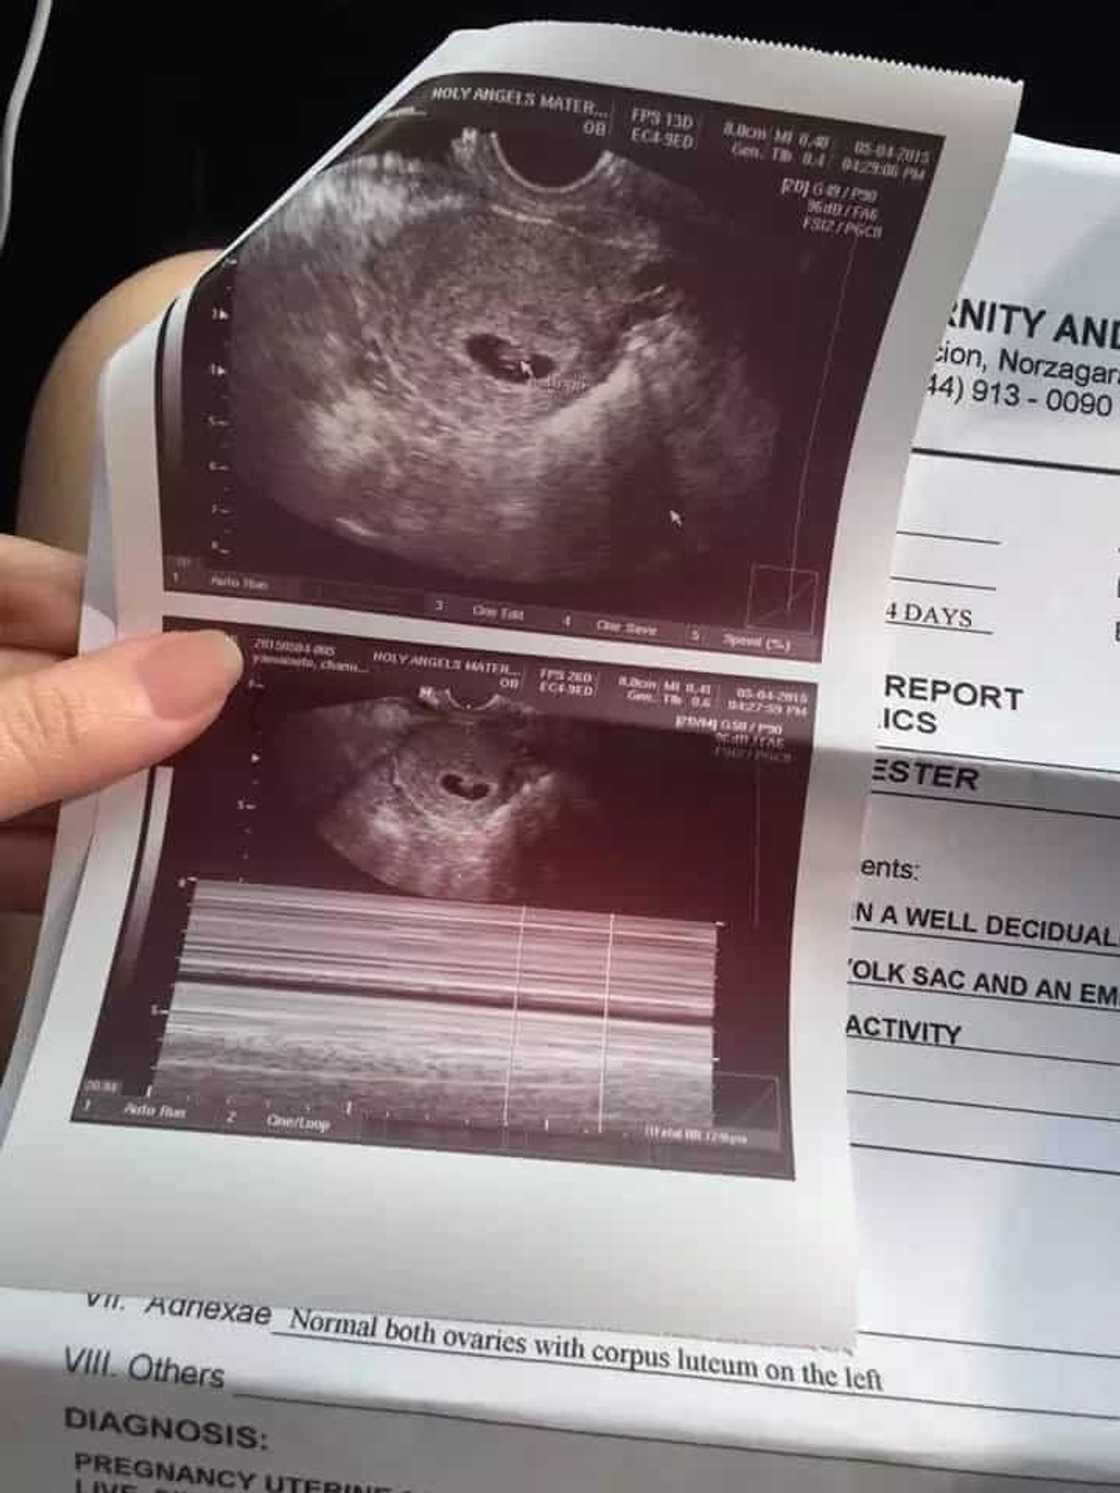

The next day, she had an ultrasound and was glad to have heard the heartbeat of her baby. She was very excited even if it meant that she would only see a small being in the results.